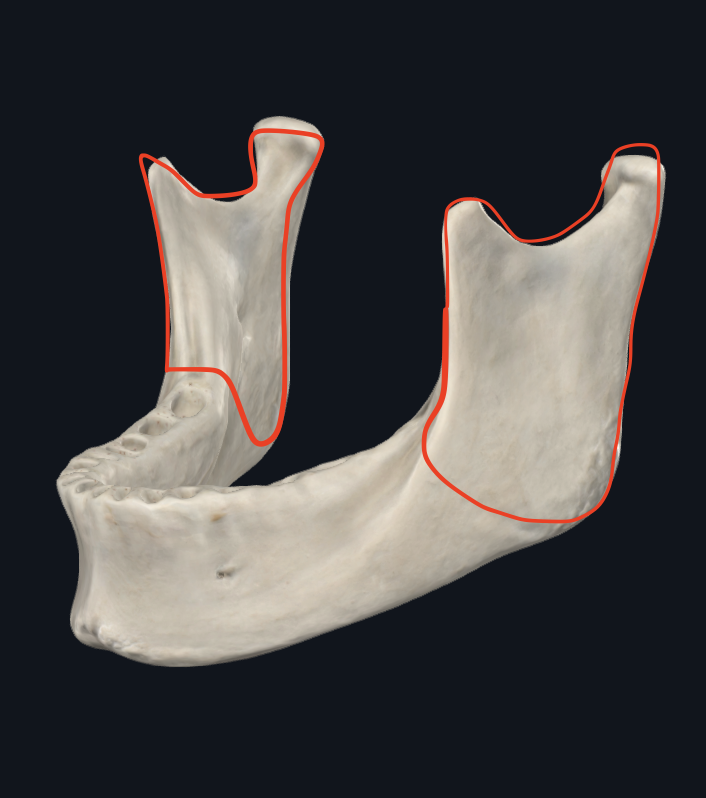

Apófisis condilar

Se puede semidislocar

Dividido en cabeza y cuello

Apófisis coronoides

Músculo temporal

Escotadura sigmoidea

Ángulo maxilar

Une el borde inferior con el borde posterior

o Gonión